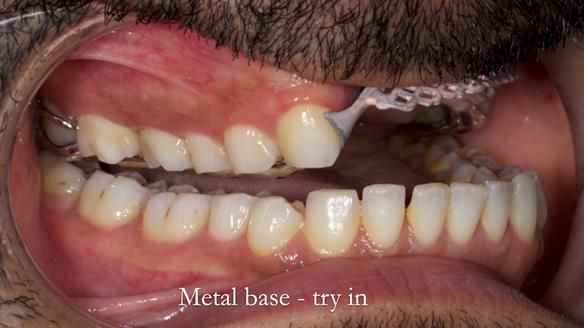

Metal based removable partial denture/occlusal stabilisation splint/obturator

The clinical situation and treatment process is shown in detail below with photographs. I (Finlay Sutton) provided the clinical work and Rowan Garstang provided the technical work.